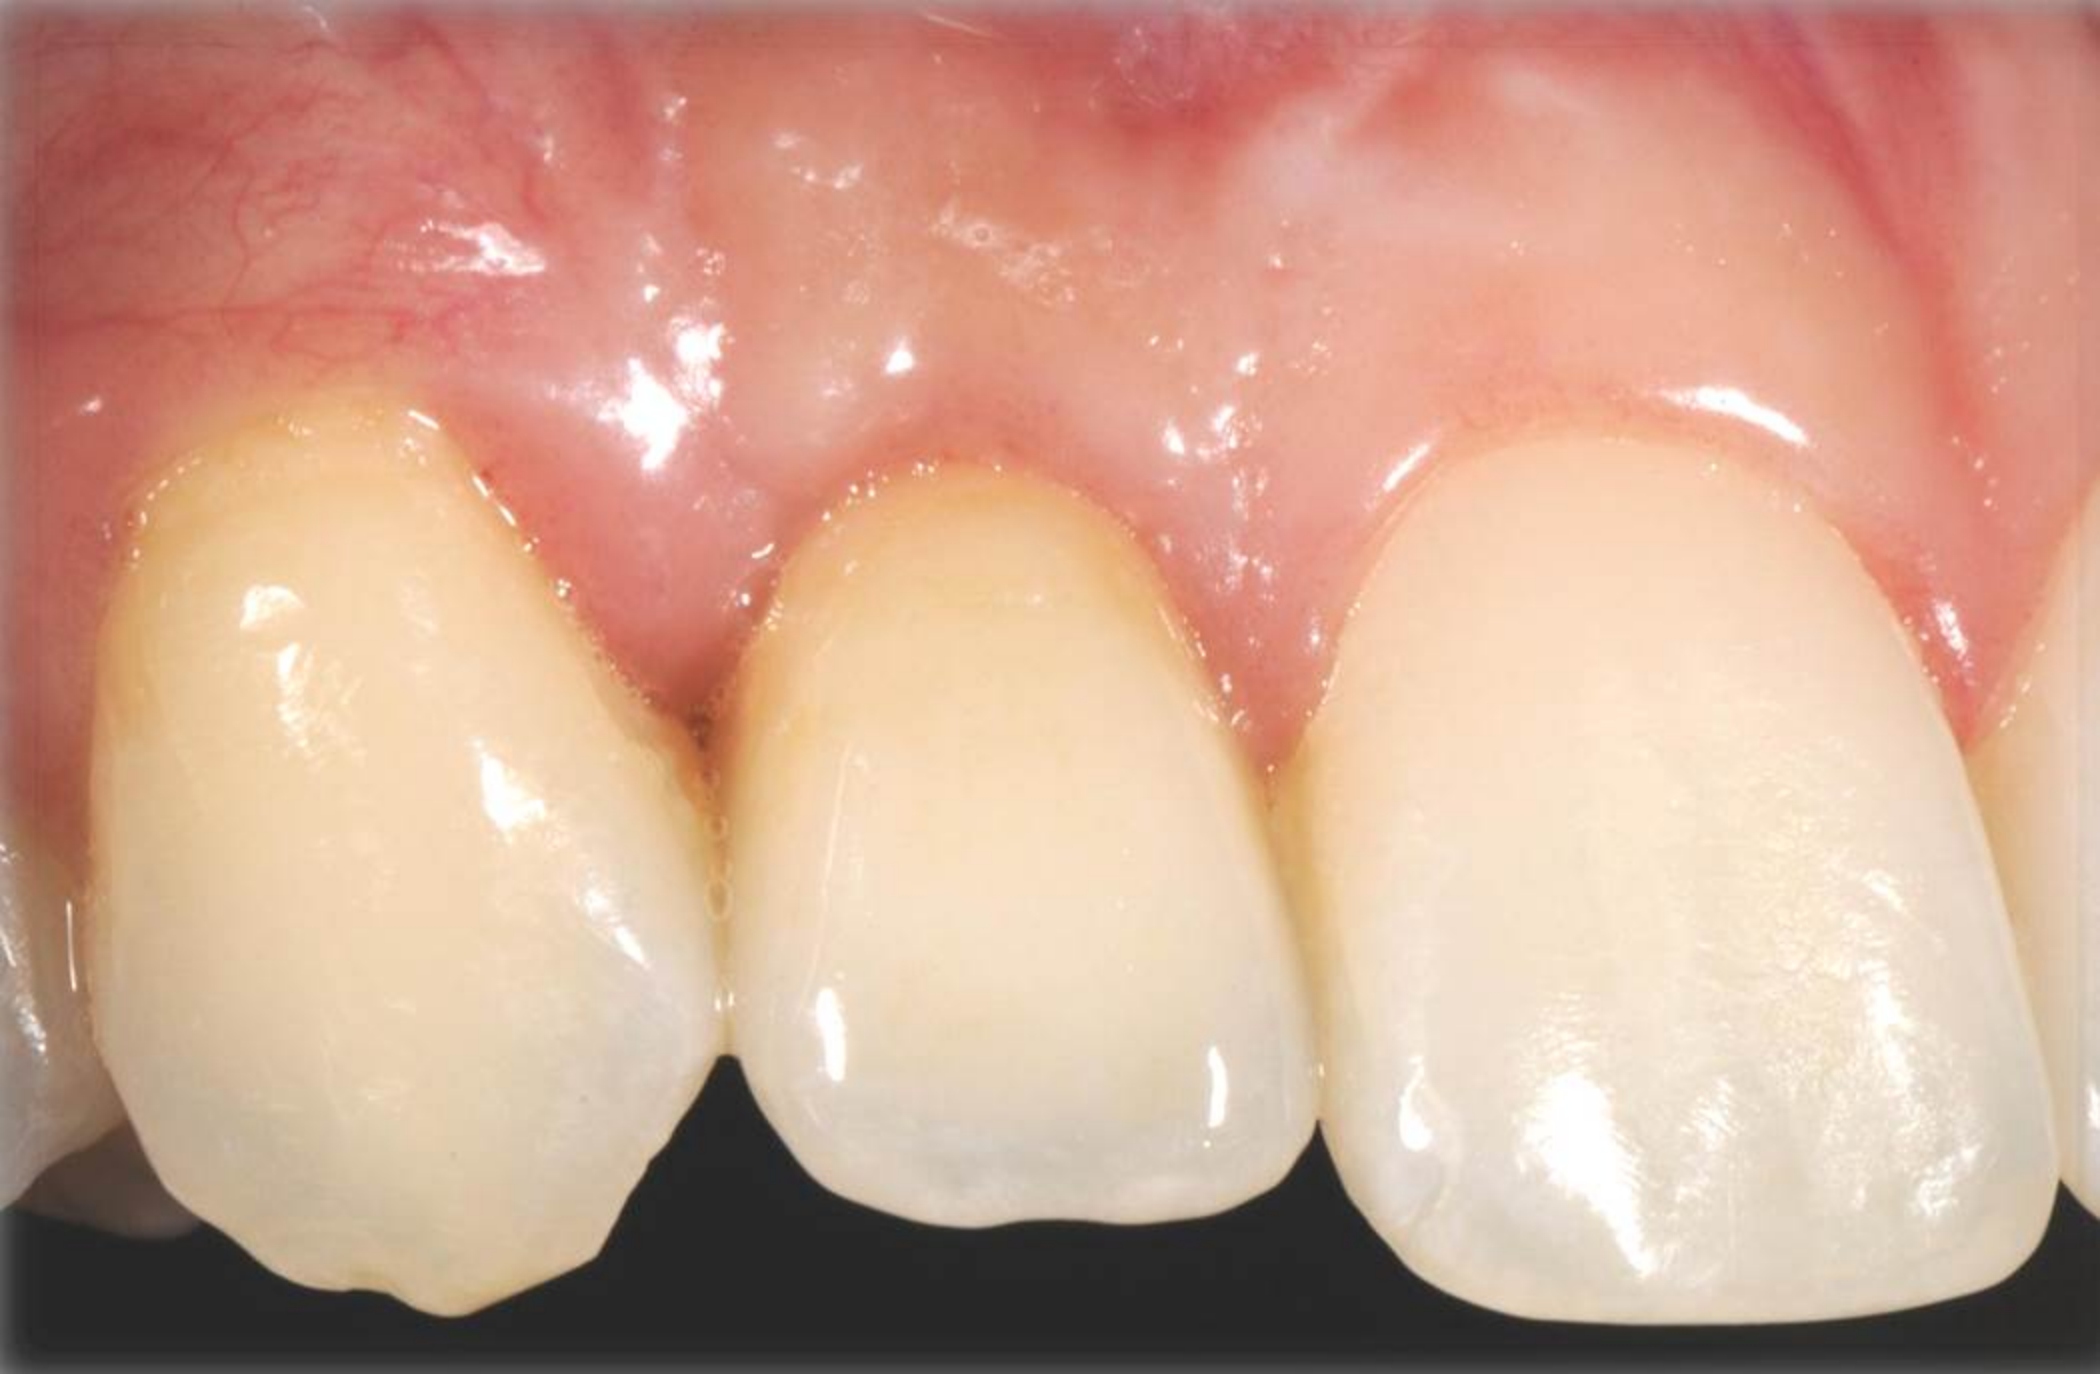

Fig 18. The final restoration after 4 months.

Figure 18